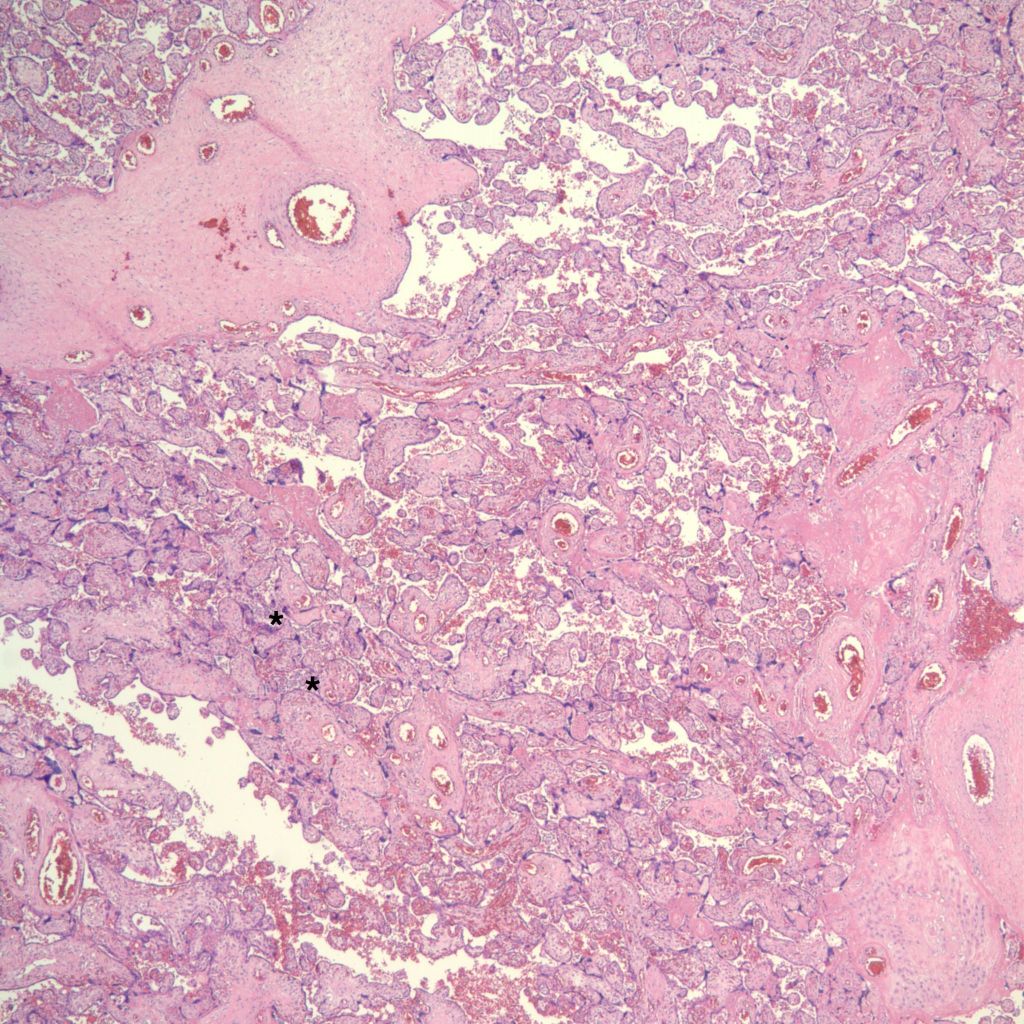

High Grade (massive) CHIV

Low Grade CHIV (5-50% of the intervillous space occupied by monocytes)